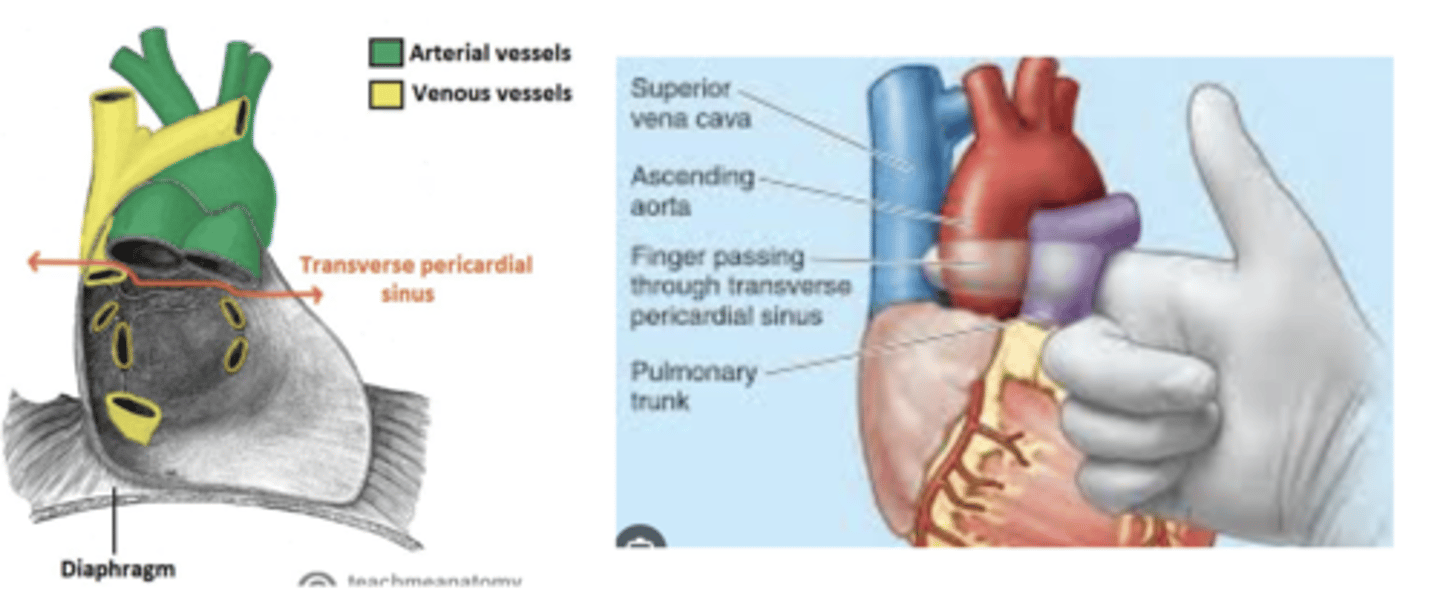

What is the transverse sinus of the pericardium ?

. space posterior to the aorta and pulmonary trunk

. anterior to vena cava

Clinical significance of the transverse sinus?

Surgeons use it during cardiac procedures.

By passing a finger or clamp through the sinus they can isolate these arteries and control blood flow to the heart during surgeries like coronary artery bypass grafting (CABG).